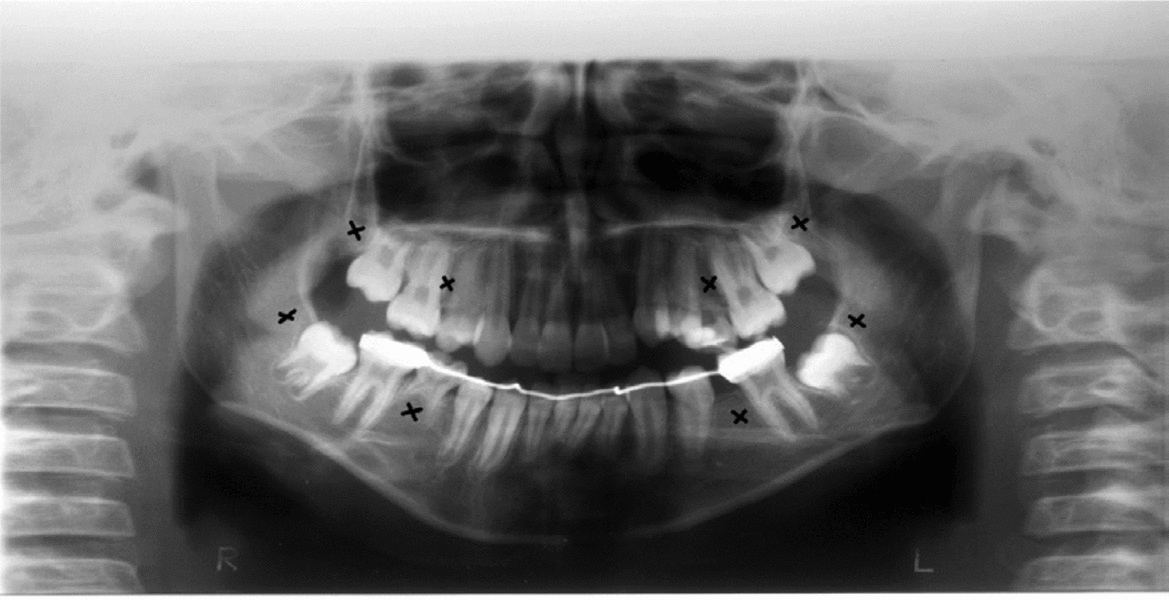

Clinical and radiographic tests revealed that patients 1 and 2 had tooth agenesis, and excluded other causes for the missing teeth, such as dental caries, periodontal disease, or aggressive trauma. Patient 1 had a congenital absence of lower second premolars and upper and lower third molars (Figure 1). In contrast, patient 2 revealed agenesis of upper and lower second premolars, as well as that of upper and lower third molars (Figure 2). Their father also had unilateral agenesis of a lower permanent incisor (data not shown).

FIGURE 1 Panoramic radiograph of patient 1 teeth in 2011; those missing are indicated with an x.